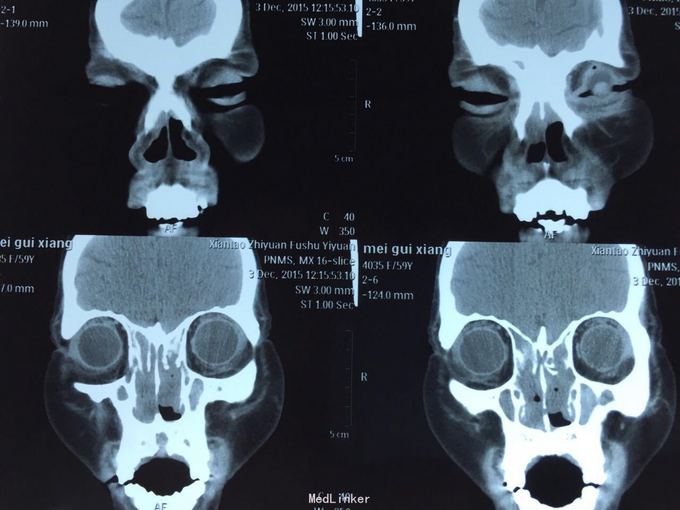

患者鼻塞分泌物增多,一年余,自诉曾于03年及09年两次鼻息肉摘除手术,现查鼻内镜双侧鼻腔可见大量息肉样物,鼻窦ct示全组鼻窦炎,鼻腔息肉。患者拟住院行第三次鼻息肉手术。